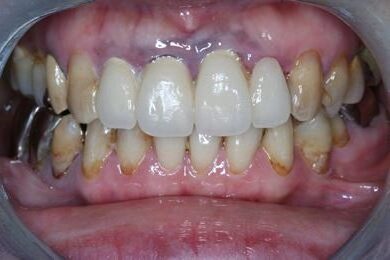

インプラントの症例写真 IMPLANT

インプラント治療+セラミック治療

| 治療内容 | インプラント3本、ジルコニアフレームオールセラミッククラウン7本(ジルコニア用土台1本)、メタルボンドセラミッククラウン3本(メタルボンド用土台3本)、ハイブリッドセラミッククラウン3本、ハイブリッドセラミックインレー3本 | ||||||||||||||||||||||||||||||||